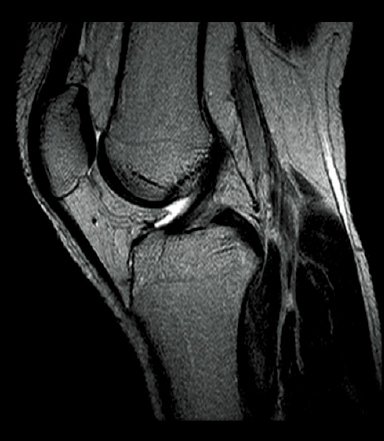

FatSat-PDWI